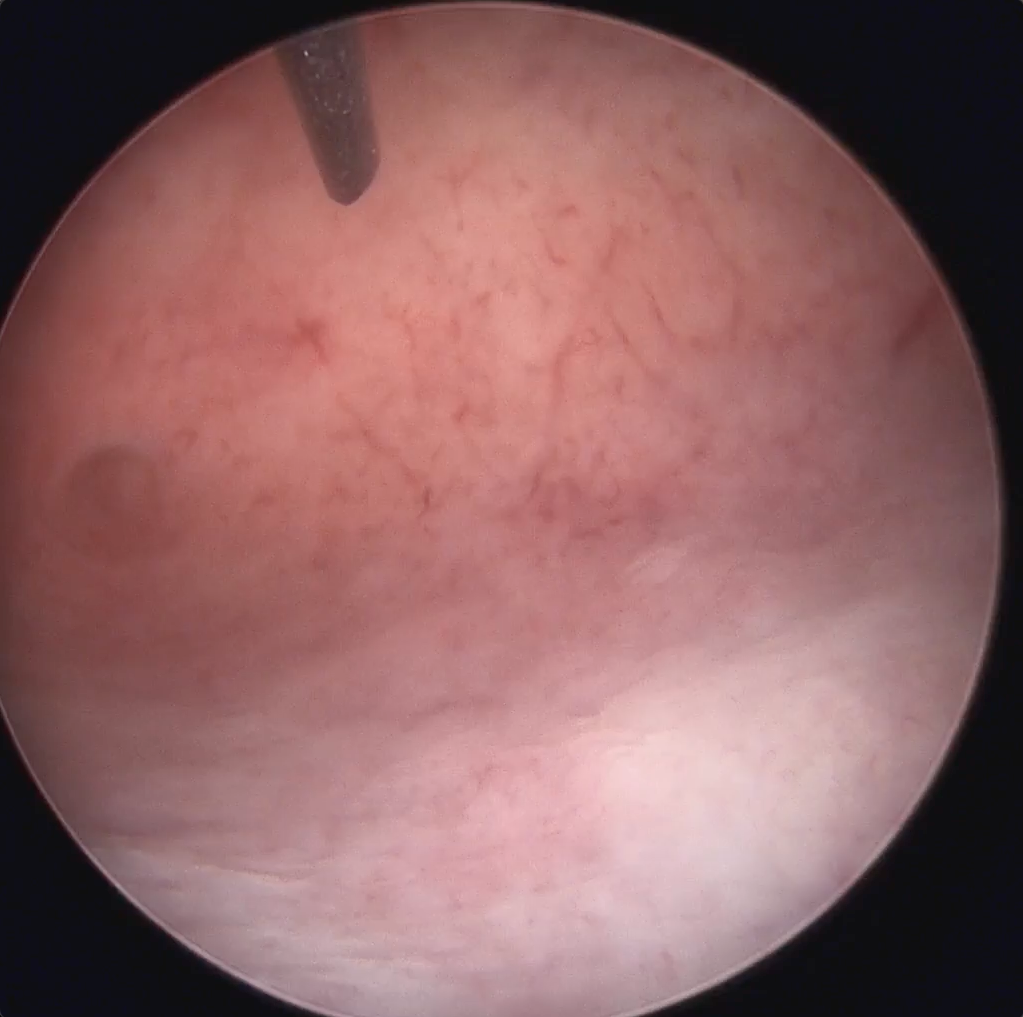

Hysteroscopic Polyp Removal with MyoSure device

This video shows the removal of an endometrial polyp using the MyoSure Lite device. The procedure is performed under direct hysteroscopic visualization in an office-based setting.

Polypectomy & Endometrial Sampling

In this video you can watch Dr. Bert Geer perform a small polypectomy including endometrial sampling.

Classical Polyp Resection

Watch Amy Garcia M.D. perform a classical MyoSure LITE polyp resection.